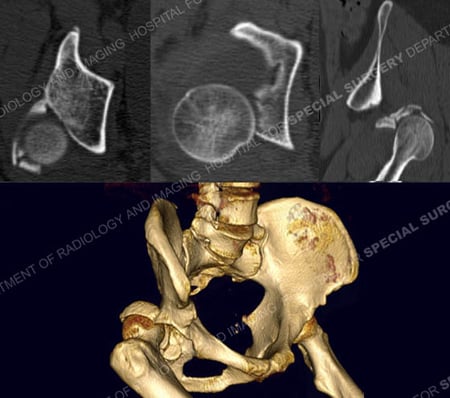

CT scan images including 3D CT reconstruction image further delineating the fracture pattern.